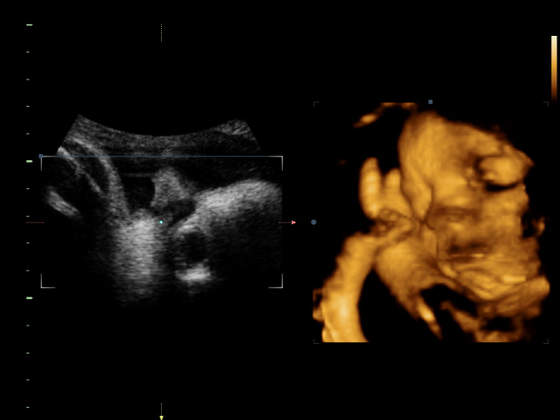

tak w ogóle to skróciła mi się szyjka, teraz ma 2.9 ale mieści się w normie, i troszkę nie podobał się mu mój twardy brzuch, na ktg nie było widać mocnych skurczów, więc są to przepowiadające i mam nie szaleć, a tak to ok, stwierdził, że dziecko jest na tyle dojrzałe, że jakby zaczął się poród to nie będziemy go zatrzymywać, na co mój mąż zareagował tak:

ooo już są, na drugim na sam koniec widać, jak otwiera paszczkę i chce się ugryźć he he